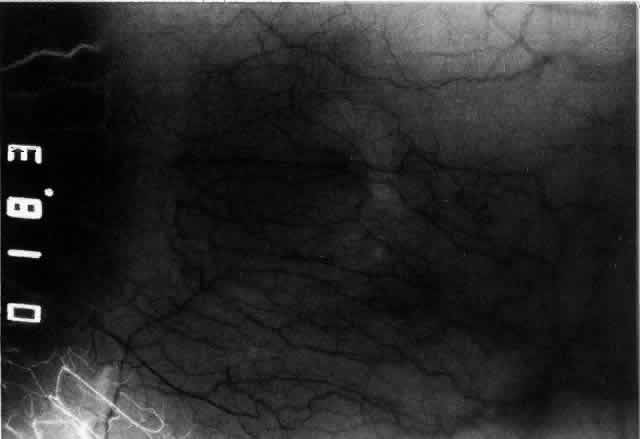

The characteristic features of necrotizing scleritis on fluorescein angiography

are hypoperfusion and, eventually, nonperfusion of the vascular

networks (Figs. 40 through 43).26 The initial changes are on the venous side of the capillary network; the

transit time of the dye increases even if the eye is red and congested. If

the disease process persists or has been present for a long time, thrombosis

and permanent vaso-occlusive changes occur. These vessels (or

the occluded capillary network) are bypassed by the opening of

anastomotic channels. New vessels in a granuloma give rise to deep intrascleral

leakage of dye (see Fig. 43). Conjunctival and episcleral involvement by the destructive change is

Fig. 42. Late arterial phase of fluorescein angiogram in a patient with necrotizing

scleritis. All the vessels except the main trunk and the vessels around

the limbal perforating vessels are occluded and remain unperfused

throughout the angiogram. Fig. 42. Late arterial phase of fluorescein angiogram in a patient with necrotizing

scleritis. All the vessels except the main trunk and the vessels around

the limbal perforating vessels are occluded and remain unperfused

throughout the angiogram.

Fig. 43. Late venous phase of angiogram of a patient with necrotizing scleritis

showing late deep leakage from vessels on the surface of the sclera and

leakage of the capillary network at the limbus and the vessels draining

it, together with poor or absent perfusion of the remaining vessels. Fig. 43. Late venous phase of angiogram of a patient with necrotizing scleritis

showing late deep leakage from vessels on the surface of the sclera and

leakage of the capillary network at the limbus and the vessels draining

it, together with poor or absent perfusion of the remaining vessels.